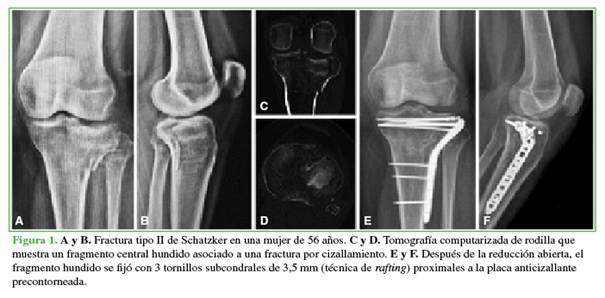

Los pacientes fueron operados en una mesa radiotransparente bajo anestesia raquídea. El abordaje anterolateral para exponer la meseta lateral se realizó en decúbito dorsal. Se utilizó una artrotomía submeniscal para visualizar la lesión y evaluar directamente la reducción. En las fracturas con hundimiento puro, el fragmento osteocondral se redujo con una pinza a través de una ventana cortical. Para el tipo II, se abrió la fractura y el fragmento deprimido se elevó en bloque utilizando un osteótomo. La reducción de la fractura se supervisó con fluoroscopia en todos los casos.

En el otro procedimiento, se restituyó la superficie articular con aloinjerto óseo impactado desde una ventana distal, se colocaron 2 tornillos canulados (de 4,5 o 6,5 mm) y luego se impactó y rellenó nuevamente con aloinjerto para ocupar el defecto metafisario (Figura 2).

En las fracturas tipo II, se colocó una placa bloqueada de bajo perfil como contrafuerte, mientras que, en las fracturas tipo III, su uso quedó a discreción del cirujano encargado.